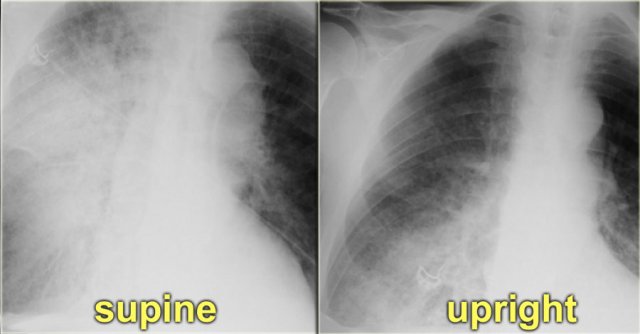

On the left a patient who first had a chest film in a supine position.

Notice the pulmonary edema, which is almost exclusively seen in the right lung.

A possible explanation for this phenomenon could be, that the patient had been lying on his right side for a while before the x-ray was taken.